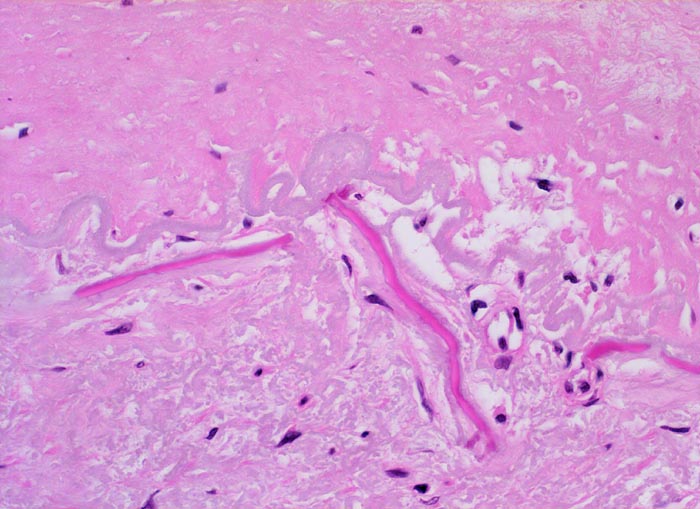

Morphologie:

Die Atherosklerose befällt Arterien vom elastischen Typ und die grossen und mittelgrossen Arterien vom muskulären Typ. Die früheste Läsion, der Lipidstreifen, besteht aus einer fokalen Akkumulation von Lymphozyten und glatten Muskelzellen und von Serumlipoprotein in Makrophagen der Intima (> 5267). Zirkulierende Monozyten infiltrieren die Intima, nehmen alteriertes LDL Cholesterin auf und wandeln sich dadurch in Schaumzellen um. Diese Läsion kann sich durch zunehmende Lipidakkumulation und Migration sowie Proliferation von Myofibroblasten zum Präatherom mit wenig extrazellulären Lipidablagerungen und schliesslich zum Atherom (> 9003) mit zentral konfluierten extrazellulären Lipidmassen (> 9004) und nekrotischem Detritus weiterentwickeln. Die eingewanderten Mediamyozyten produzieren extrazelluläre Matrix, welche über dem Atheromkern aus extrazellulärem Lipid, Schaumzellen, Kalziumsalzen und Zellschutt eine fibröse Deckplatte bildet. Die atheromatöse Plaque kann narbig umgebaut werden, dystroph verkalken und konsolidieren oder zu einer komplizierten Plaque fortschreiten. Komplizierte Läsionen sind charakterisiert durch Ulzeration, Thrombose oder Plaqueeinblutungen. Bei einer Verletzung des Endothels oder einer Ruptur der fibrösen Deckplatte kommt der thrombogene Inhalt des Lipidkerns in Kontakt mit dem zirkulierenden Blut und es bildet sich eine Gefässthrombose. Wiederholte Rupturen mit nachfolgender Organisation der Thrombose vergrössern die Plaque und führen zu einer zunehmenden Gefässeinengung. Bei langsam gewachsenen schweren Stenosen bildet sich oftmals ein guter Kollateralkreislauf aus, welcher bei plötzlichem Gefässverschluss einen Infarkt im Versorgungsgebiet der verschlossenen Arterie verhindern kann. Grosse inter- und intraindividuelle Unterschiede bezüglich der relativen Anteile von weichen atheromatösen und derben fibrotischen bzw. verkalkten (> 4557) Bestandteilen der Plaques bestimmen wesentlich die Stabilität bzw. Vulnerabilität der Läsionen. Der Lipidanteil liegt bei rupturierten Plaques generell höher als bei Plaques mit intakter fibröser Deckplatte.